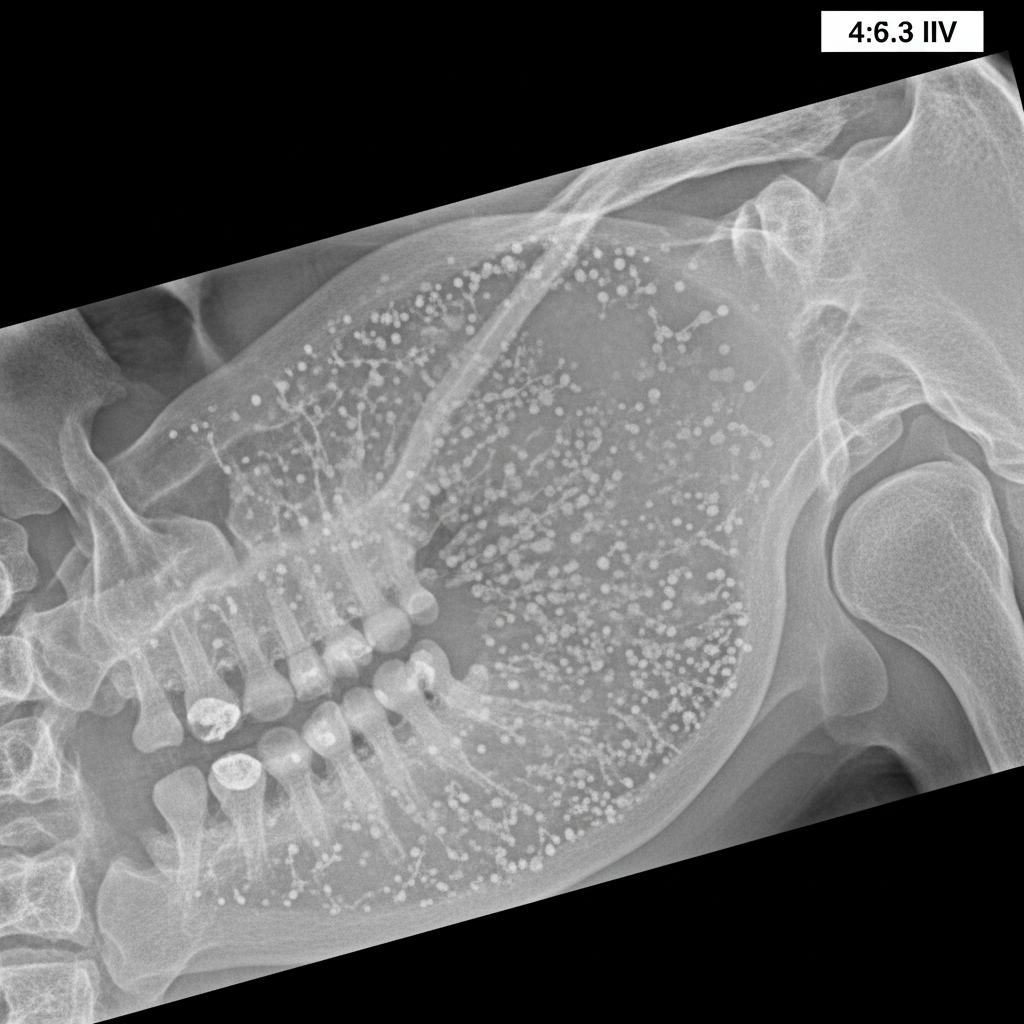

A sialography report of a 46-year-old female is provided. Based on the findings, what is the most likely diagnosis?

Explanation: ***Sjogren syndrome*** - Classic sialographic findings include **punctate** and **globular sialectasias** creating a characteristic **"snowstorm"** or **"cherry blossom"** pattern due to acinar destruction. - Typically affects **middle-aged females** and is associated with **autoimmune sicca syndrome** causing dry mouth and eyes. *Sialolithiasis* - Sialography would show a **filling defect** or **calculus shadow** within the ductal system, not the diffuse pattern seen in Sjögren syndrome. - Usually presents with **unilateral pain** and **swelling** during meals, particularly affecting the submandibular gland. *Normal parotid appearance* - Normal sialogram shows **smooth ductal outlines** with normal branching pattern and no evidence of sialectasias or strictures. - Would not demonstrate the **punctate** or **globular** changes characteristic of autoimmune salivary gland disease. *None of the above* - The sialographic findings described are pathognomonic for **Sjögren syndrome** in the appropriate clinical context. - The **punctate/globular sialectasias** pattern is a well-established diagnostic criterion for this **autoimmune condition**.